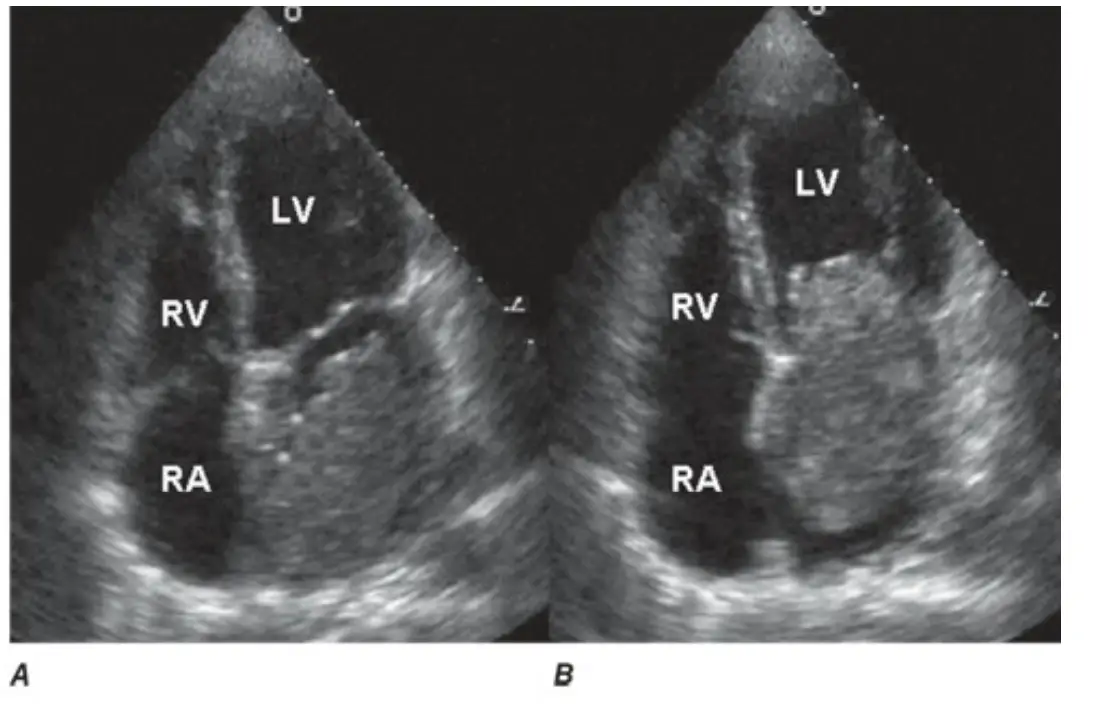

一位42歲女性病患,主訴躺臥時某特定姿勢會伴隨眼前發黑的徵兆(black out)。臨床上症狀還包括倦怠,體重減輕身體檢查時,心臟聽診於心尖部舒張中期有一低頻心音,並有輕微杵狀指 (digital clubbing)。心臟超音波檢查如附圖,A圖為心室收縮期呈像,B圖為心室舒張期呈像 [RA=右心房;RV=右心室;LV=左心室]。請問該病患最有可能的診斷為?

從兩張心臟超音波的四腔切面(apical four-chamber view)可觀察到:

- 圖A(收縮期)時,心室收縮將左心房內之異常回聲結構往心房方向牽引,使得右心房(RA)及右心室(RV)與左心室(LV)腔室未見明顯阻塞。

- 圖B(舒張期)時,影像中左心房內可見一個大而有蒂的回聲不均結構,順重力及心室舒張拉力,自左心房墜入左心室,幾近填滿二尖瓣口,顯示動態性的瓣口阻塞。

此種舒張期移動性腫塊,表徵典型左心房myxoma在舒張期經瓣口擺動致血流受限之影像表現。